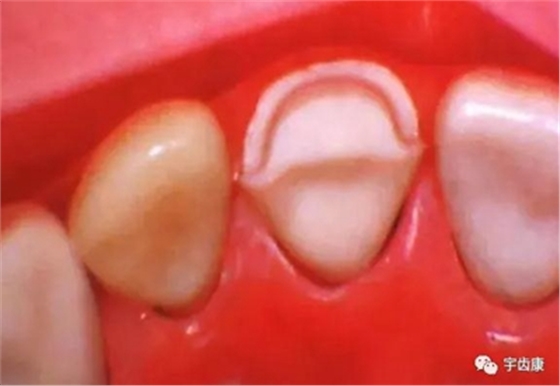

牙體各個(gè)面的解剖厚度

烤瓷牙結(jié)構(gòu)知識(shí)

烤瓷牙的設(shè)計(jì)方式